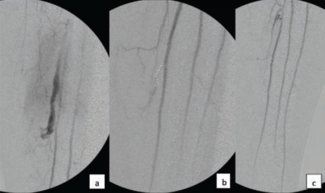

A re-bleeding retroperitoneal hematoma following surgical exploration for penetrating trauma is a challenging clinical scenario.